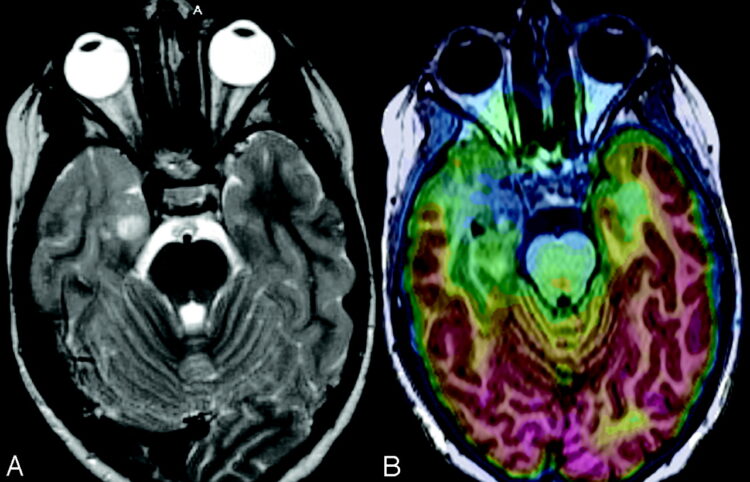

PET

PET or positron emission tomography is yet another type of tomography technique that uses radiation for the base of it.

This particular type uses an atom that emits a particle called a positron. This atom is actually radioactive by nature and the positron can be absorbed by multiple means.

Most PET scans are used to include the likes of brain imaging studies with a focus on uncovering cancer. Other areas also include the lungs and liver, breasts, colon, ovaries, and others.